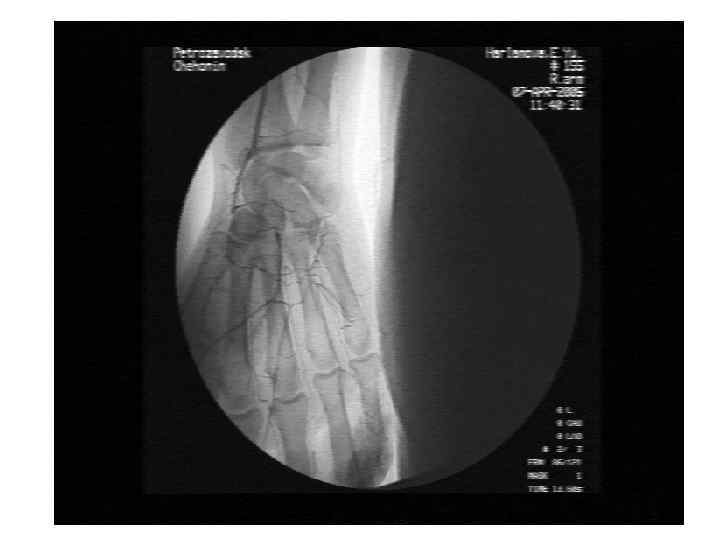

Некротический васкулит при системной красной волчанке